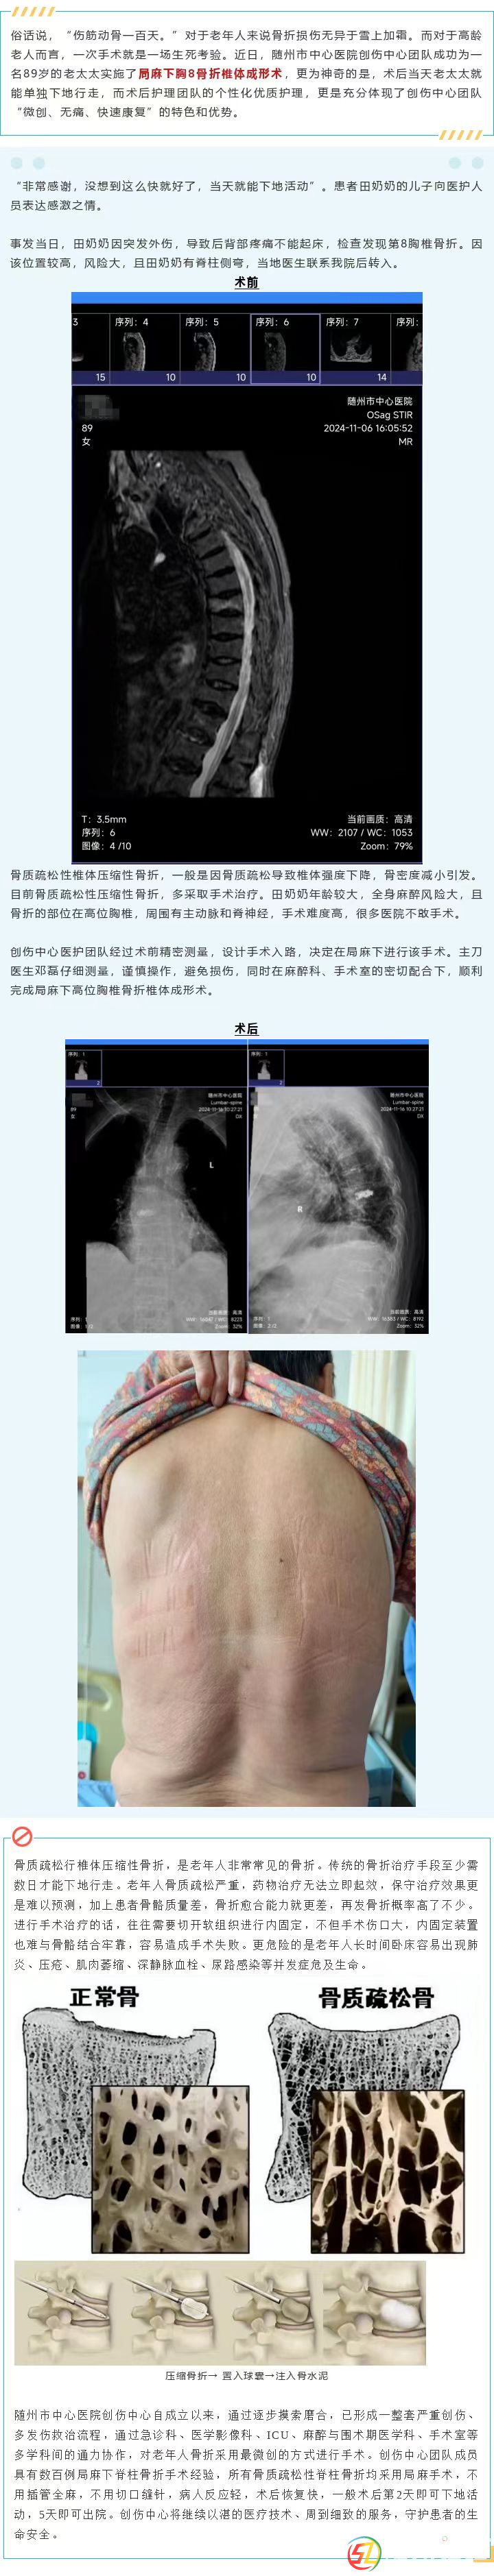

【微創(chuàng)技術(shù)】九旬老人胸椎骨折,術(shù)中局麻,當天即下地行走!這是什么神操作?